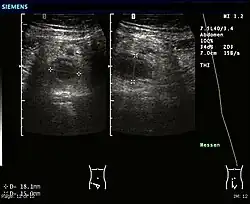

Ultrasound

An ultrasound image of acute appendicitis in December 2008.

Abdominal ultrasonography, preferably with doppler sonography, is useful to detect appendicitis, especially in children. Ultrasound can show the free fluid collection in the right iliac fossa, along with a visible appendix with increased blood flow when using color Doppler, and noncompressibility of the appendix, as it is essentially a walled-off abscess. Other secondary sonographic signs of acute appendicitis include the presence of echogenic mesenteric fat surrounding the appendix and the acoustic shadowing of an appendicolith.[59] In some cases (approximately 5%),[60] ultrasonography of the iliac fossa does not reveal any abnormalities despite the presence of appendicitis. This false-negative finding is especially true of early appendicitis before the appendix has become significantly distended. Also, false-negative findings are more common in adults where larger amounts of fat and bowel gas make visualizing the appendix technically difficult. Despite these limitations, sonographic imaging with experienced hands can often distinguish between appendicitis and other diseases with similar symptoms. Some of these conditions include inflammation of lymph nodes near the appendix or pain originating from other pelvic organs such as the ovaries or Fallopian tubes. Ultrasounds may be either done by the radiology department or by the emergency physician.[61]